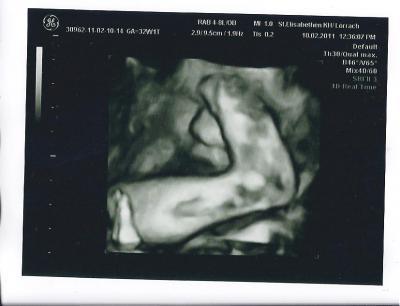

Hatten heute Geburtsbesprechung im KH und endlich hat Tochti sich Mal gezeigt. Sie hat zwar einen Fuss im Gesicht, aber man sieht Mal was.

Bild zu Juhuuuuu endlich ein Bild - Forum für April - Mamis

wahnsinn wie die kleinen sich verbiegen können.... tolles bild....wünsch dir noch eine schöne rest schwangerschaft......